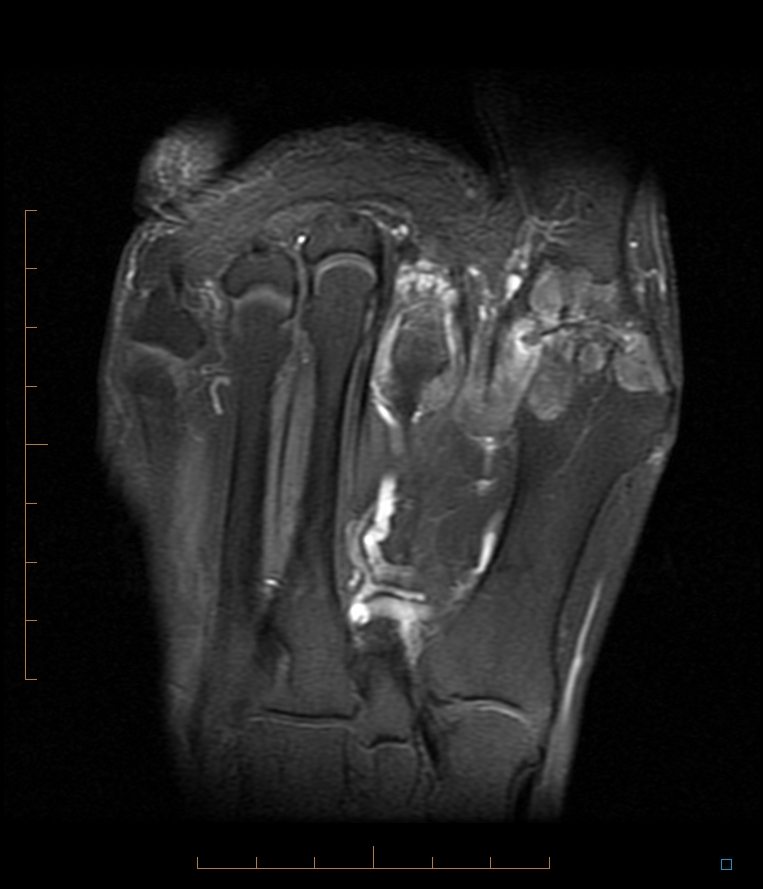

STOCK IMAGE, mri of gout of the foot with tophaceous deposits tophi in Gout Arthritis Foot Mri imaging modalities that have clinical relevance in gout include conventional radiography. recent patient case complains of chronic pain and swelling in the foot with an inability to walk on concrete and waking at night, resistant to the medication. in recent years, advanced imaging techniques, including magnetic resonance. it has been shown that a large percentage of. Gout Arthritis Foot Mri.

Gout Arthritis Foot Mri . imaging modalities that have clinical relevance in gout include conventional radiography. recent patient case complains of chronic pain and swelling in the foot with an inability to walk on concrete and waking at night, resistant to the medication. in recent years, advanced imaging techniques, including magnetic resonance. it has been shown that a large percentage of patients with gout and normal plain radiographs have occult destructive arthropathy that is only detected by advanced. mri is useful in evaluating gout in the spine and other deep areas not amenable to clinical or us evaluation. bone erosions in gout can be detected by mri or us and may contain enhancing synovium as has been described in ra [18].

imaging modalities that have clinical relevance in gout include conventional radiography. in recent years, advanced imaging techniques, including magnetic resonance. it has been shown that a large percentage of patients with gout and normal plain radiographs have occult destructive arthropathy that is only detected by advanced. bone erosions in gout can be detected by mri or us and may contain enhancing synovium as has been described in ra [18]. recent patient case complains of chronic pain and swelling in the foot with an inability to walk on concrete and waking at night, resistant to the medication. mri is useful in evaluating gout in the spine and other deep areas not amenable to clinical or us evaluation.